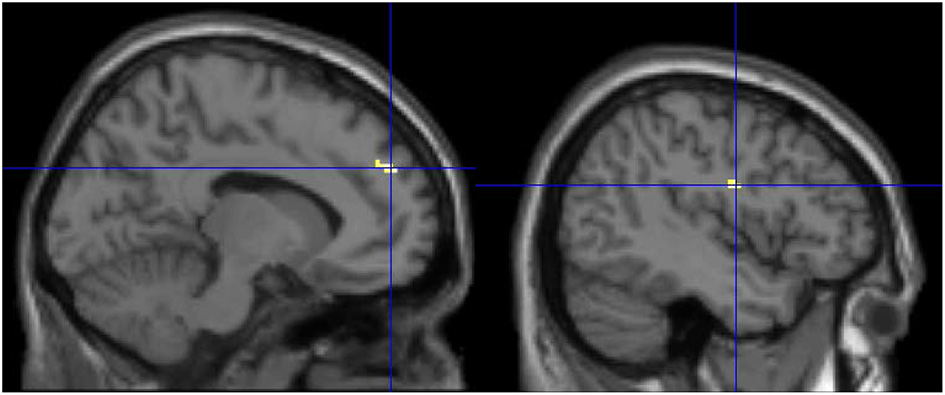

To examine the effect of training in each group, the post-training minus pre-training contrast was examined. It showed that the block play group had increased activation in the anterior lobe of the cerebellum extending into the right parahippocampus and the bilateral fusiform gyrus (see Figure 3; Table 2) after block play training than prior to training. The board game group failed to show any significant activation when comparing the pre- and post-scans, analogous to the behavioral finding of no effects of training.

Figure 3

The post- minus pre-training contrast for the block play group. Increased activation is observed in the anterior lobe of the cerebellum, the parahippocampus and the fusiform gyrus after training for the block play group.